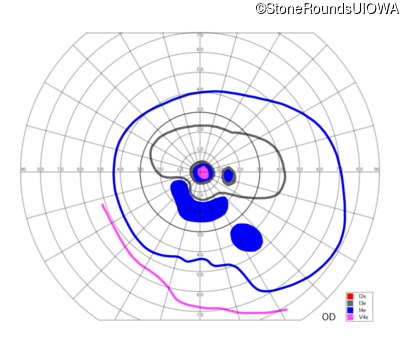

AR Stargardt Disease (IIA)

AR Stargardt Disease (IIA)

| Age at visit: 12 years |

| Age at visit: 13 years |

| Age at visit: 15 years |